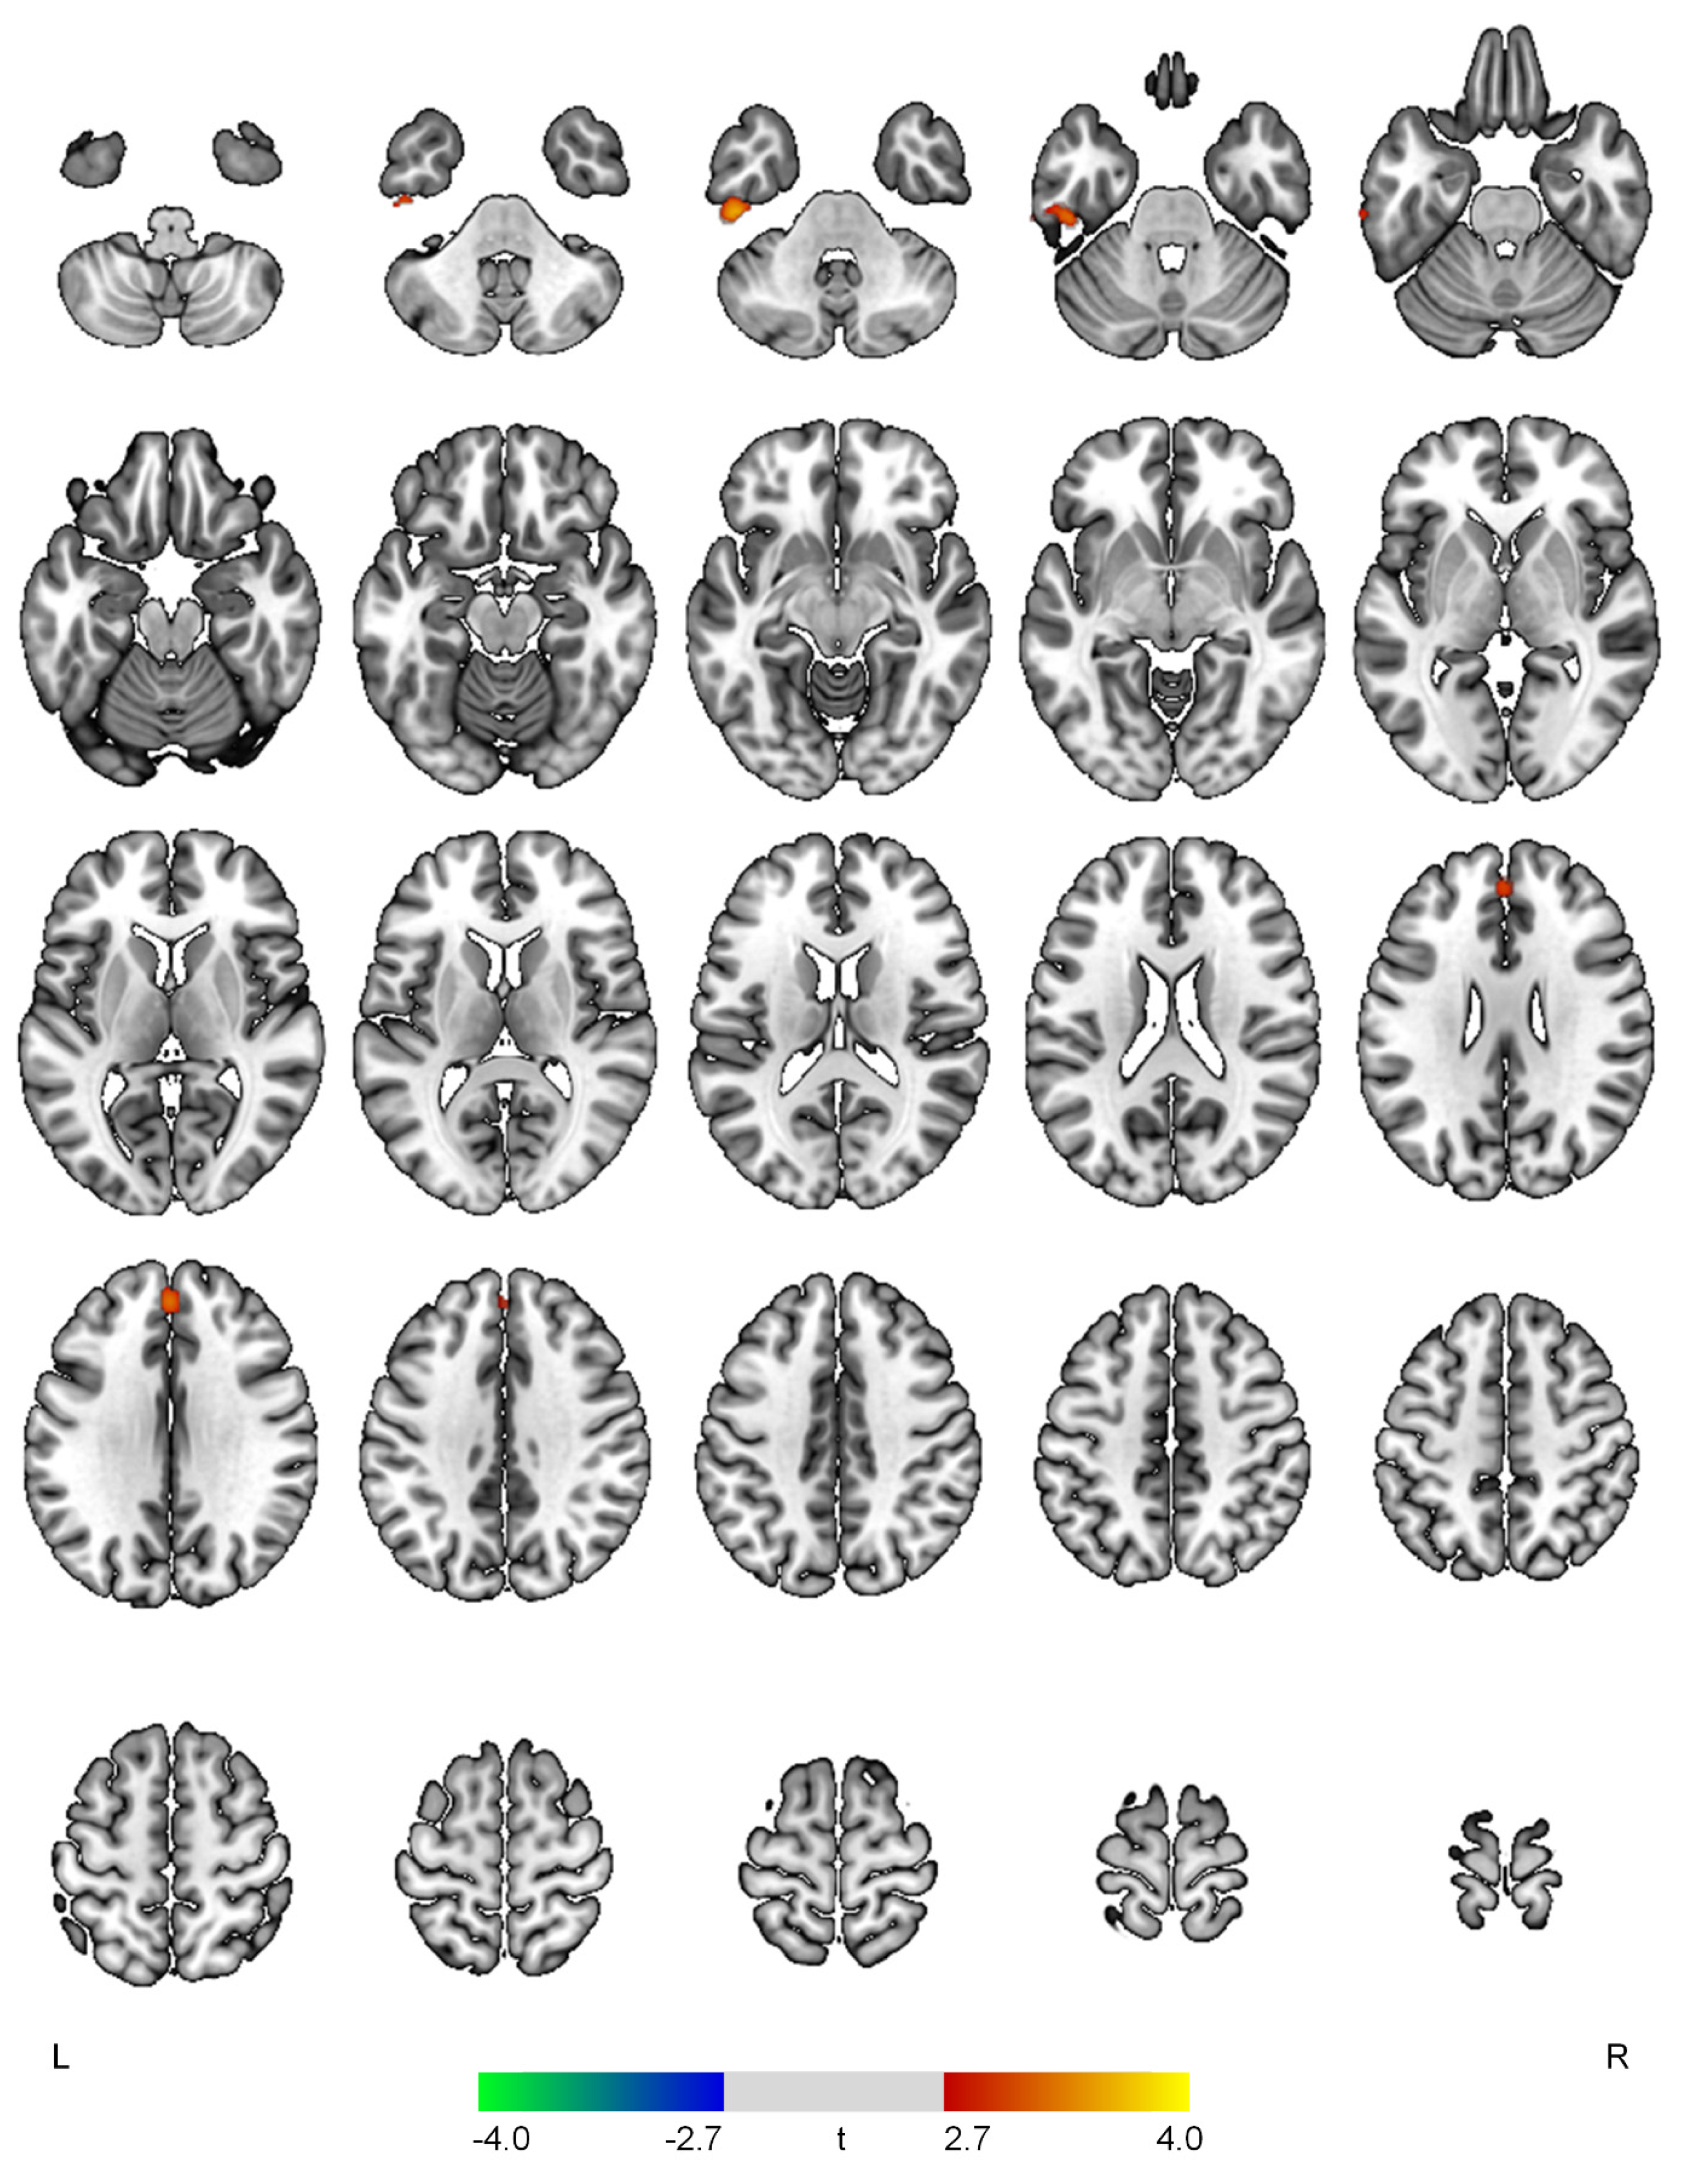

Figure 3.

Positive (red-yellow) or negative (blue-green) correlations between regional cerebral blood flow and the hyperactivity domain in patients with early Alzheimer’s disease. The color bar represents t values at each voxel. L—left; R—right.

The hyperactivity scores demonstrated positive correlations with rCBF in the left inferior temporal gyrus (t = 3.66, p < 0.001) and superior frontal gyrus (t = 3.30, p = 0.001) (Figure 3).

In the current study, the hyperactivity symptom domain was positively correlated with rCBF in the superior frontal and inferior temporal gyri that are implicated in inhibition of impulsive thoughts and visual processing of negative emotions, respectively [28,29]. The hyperactivity symptom in AD is one of the most difficult symptoms to manage and may cause a substantial burden for the caregivers [30]. However, as compared to other symptoms in AD, the neural correlates of the hyperactivity domain in AD have remained less studied [30]. Some studies reported atrophy or hypometabolism of the prefrontal-subcortical circuit in AD patients with various hyperactivity symptoms [7,9]. Another study suggested that higher levels of agitation/aggression were associated with lower gray matter volume of the superior frontal and inferior temporal gyri [31]. However, increased glucose metabolism of the superior frontal gyrus was associated with the hyperactivity symptom domain in early-onset AD [12]. Furthermore, a recent pilot work in AD found a positive correlation between hyperactivity and cortical excitability in the dorsolateral prefrontal cortex [32]. These inconsistencies may stem from methodological issues, such as sample characteristics, evaluation methods of NPSs, and neuroimaging techniques. The implications of increased rCBF in the prefrontal and temporal regions among AD patients with hyperactivity should be further investigated.